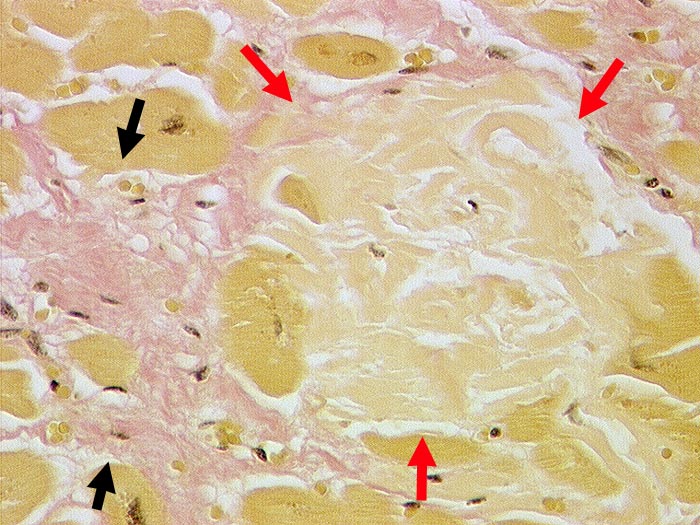

Senile Amyloidose des Myokards

Scholliges azelluläres Amyloid zwischen den Myokardfasern. Daneben feinfleckige Fibrose.

Koronare Herzkrankheit. Arterielle Hypertonie.

Histologie